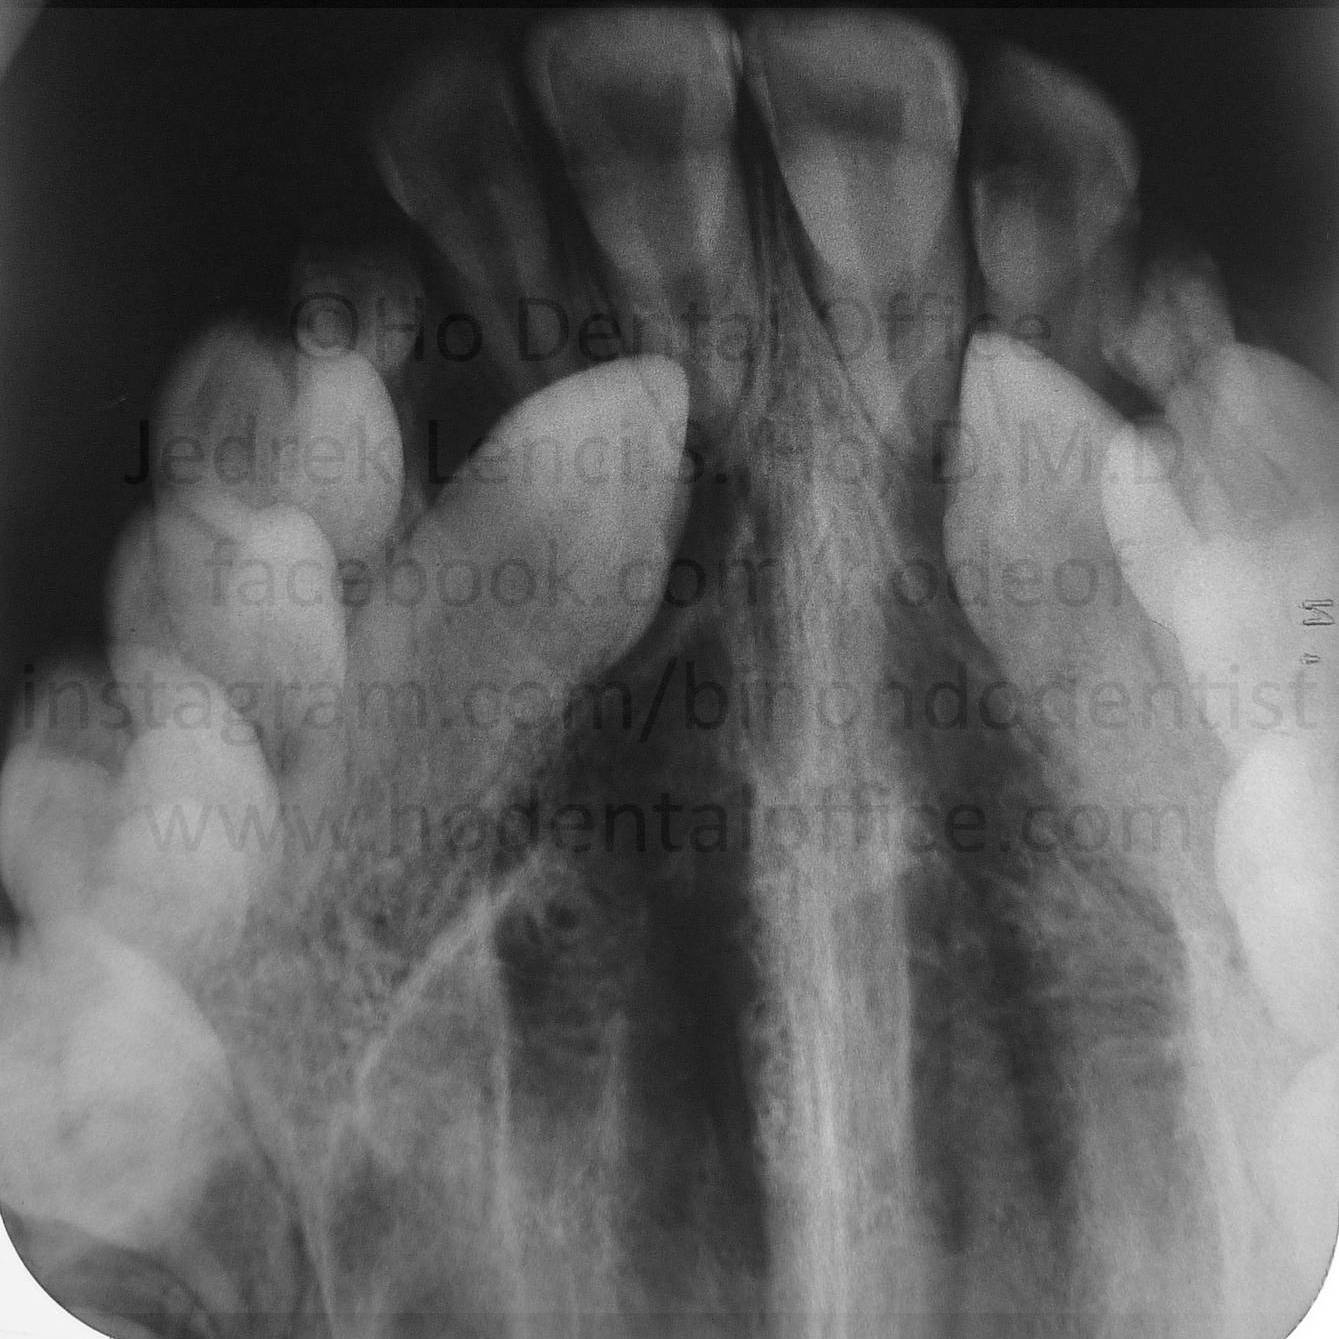

upper canine tooth

- Since the canines are very important foundational tooth crucial to the shape and anatomy of the face, most dentists / orthodontists would attempt to surgically expose and orthodontically align them into their proper position.